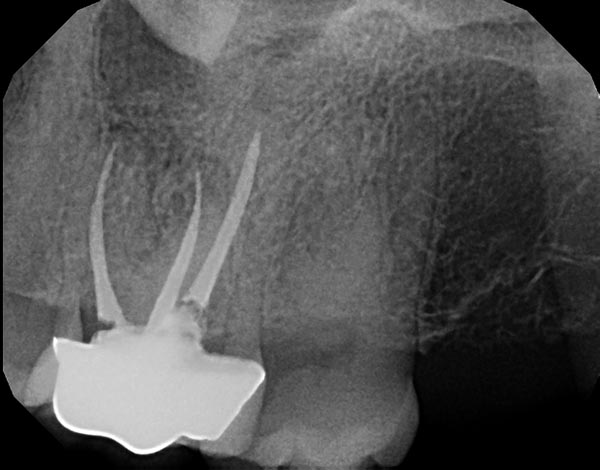

Fig. 2a: A distal angled preoperative image shows a well-defined radiolucency at the MB root apex and the previous root filling is off center, suggesting an untreated ML canal. Fig. 2b: An axial view of a CBCT clearly demonstrating the missed ML canal. Fig. 2c: Re-treatment was completed and the final shape of the canals was achieved using WaveOne Gold from Dentsply Sirona, a reciprocating, single file system that has a variable taper. Fig. 2d: At six-month recall, the tooth was asymptomatic and bone healing was complete as the PDL space and trabecular pattern were normal.

Fig. 2a